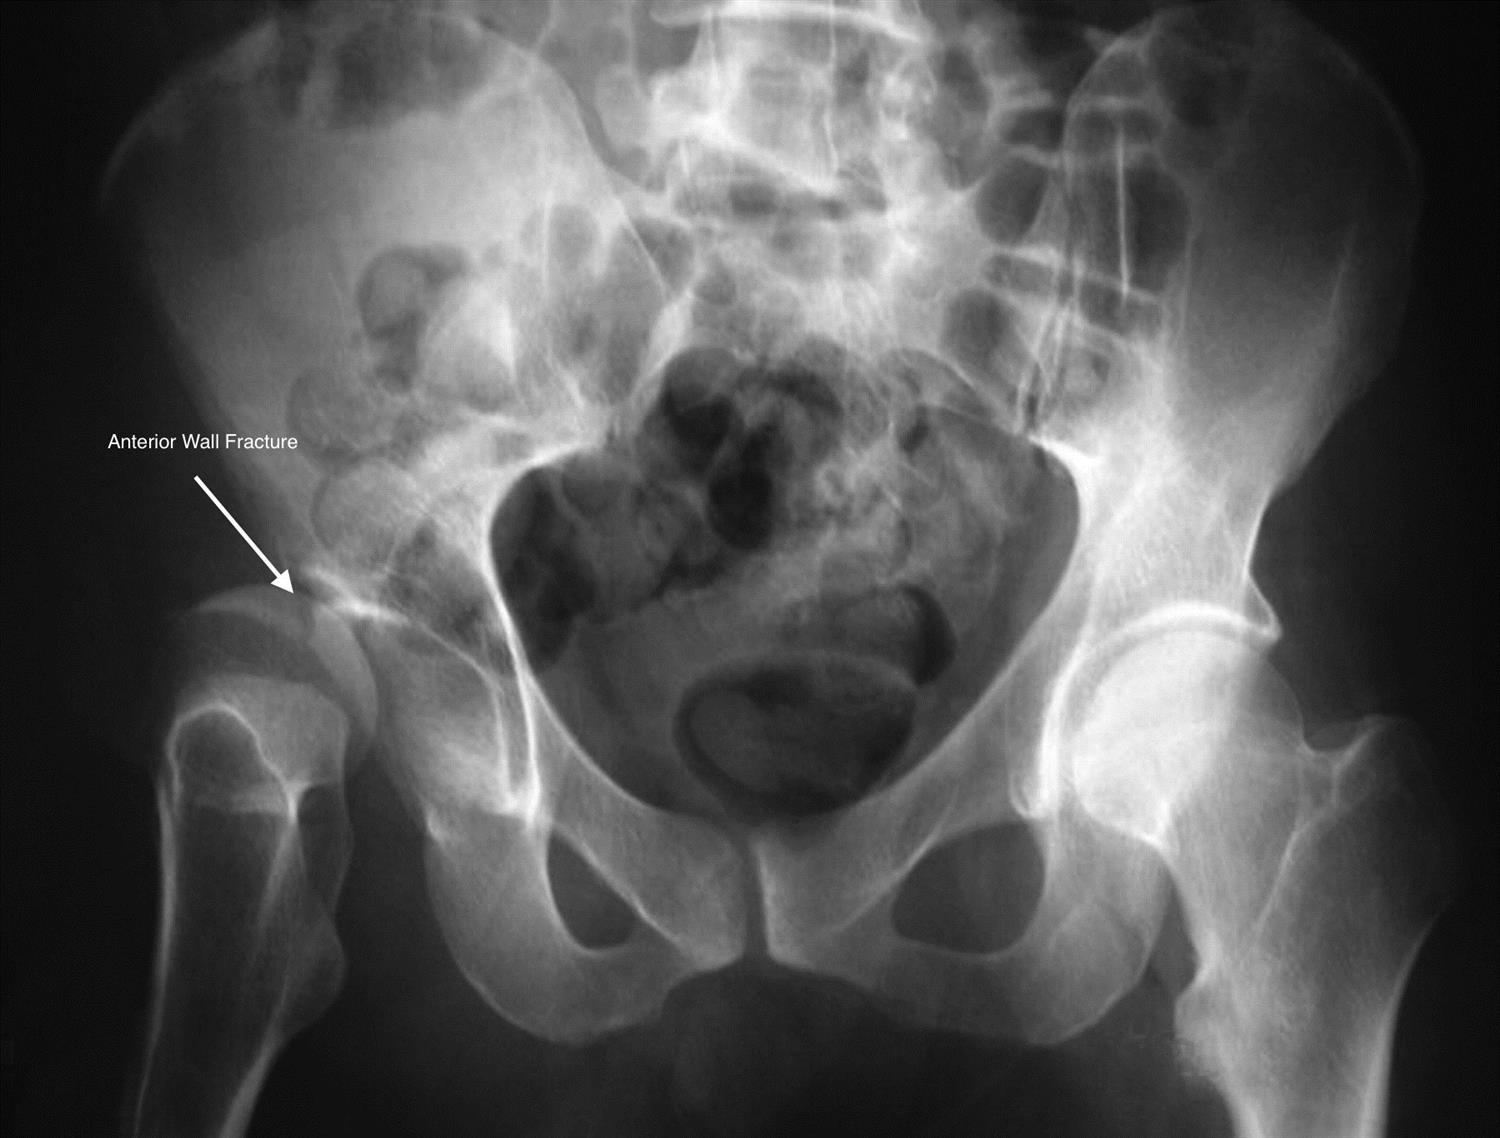

Acetabular Fractures